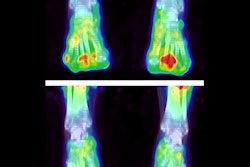

On day 23 and day 37, increased uptake (A) is noted in the front and hind paws of this mouse with collagen-induced arthritis. Graph shows predictive performance (B) of F-18 FEDAC uptake on day 23 for the development of clinical arthritis. ROC = receiver operating characteristic; Sn = sensitivity; Sp = specificity. Images courtesy of Seoul National University and Ewha Womans University.The preliminary results suggest that F-18 FEDAC could help visualize active inflammation in arthritic joints by targeting TSPO expression in activated macrophages, and it may be useful when rheumatoid arthritis is suspected.

For the study, the researchers tested F-18 FEDAC in a mouse model, using both the novel tracer and FDG-PET. They found increased TSPO messenger RNA and protein expression in activated macrophages, and there was greater uptake of F-18 FEDAC in activated macrophages than nonactivated cells. The uptake of F-18 FEDAC increased earlier in arthritic joints (day 23); however, the uptake of FDG increased later (day 37), reaching a higher level.